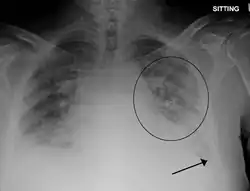

| Peripheral edema in the lower extremity that can result from volume overload following large volume blood transfusions. | |